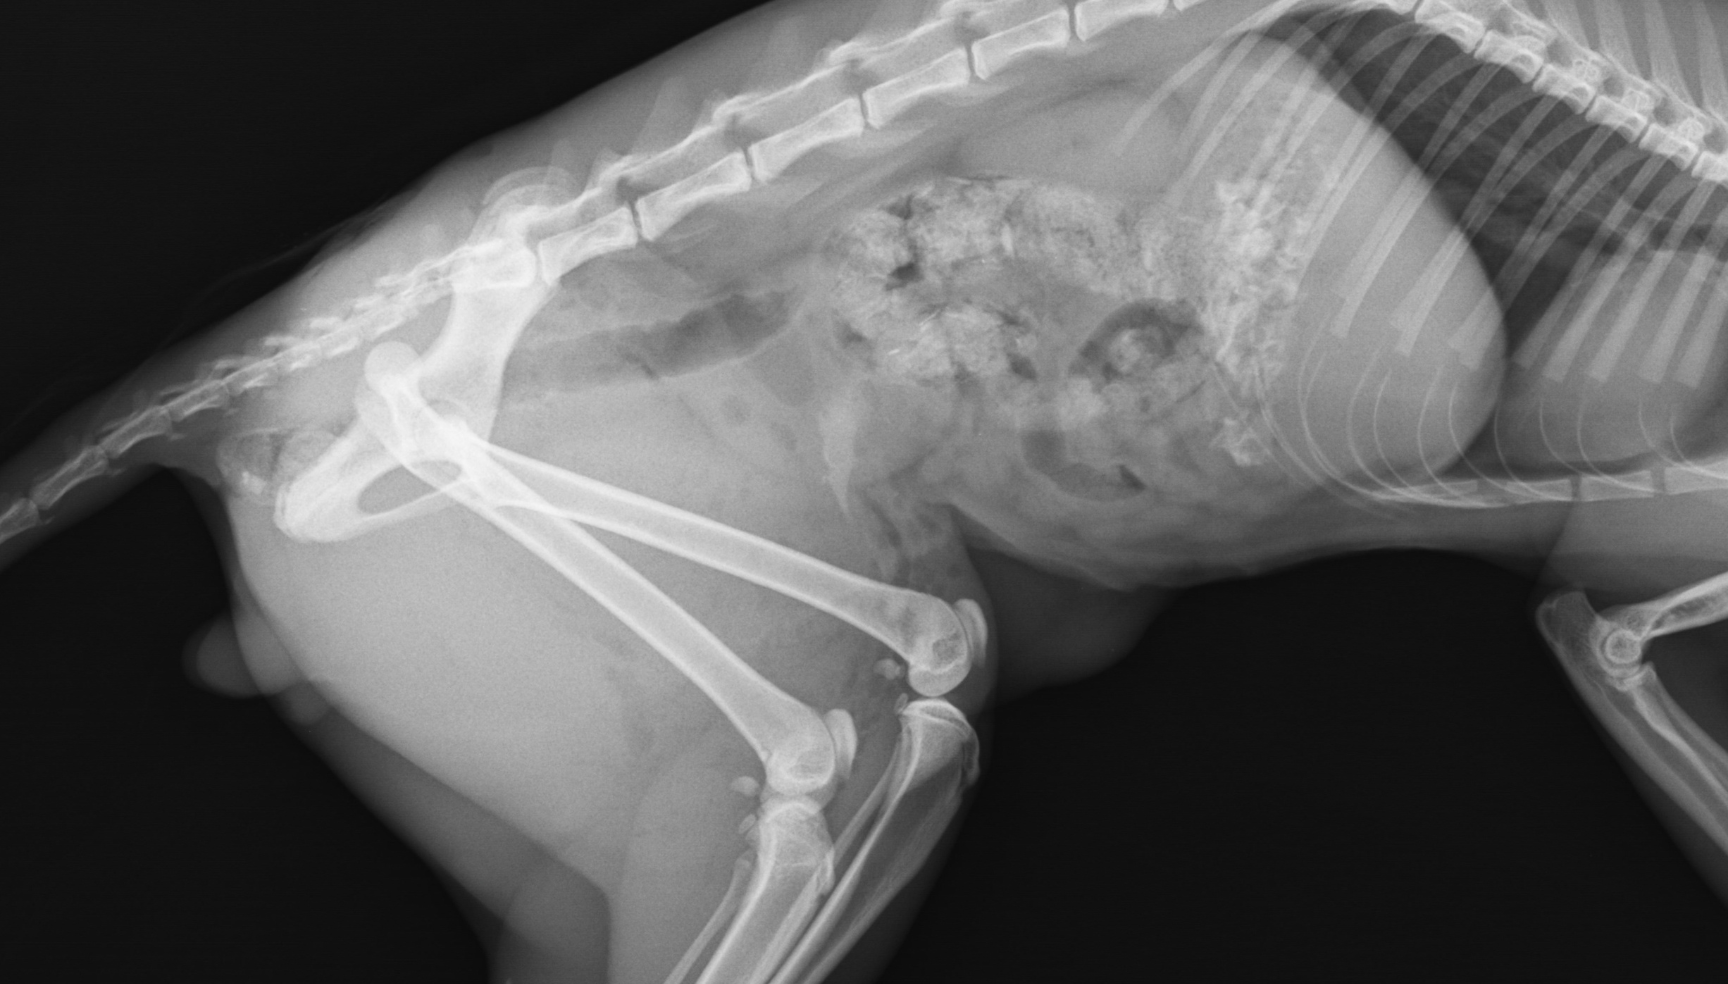

Layanan Lab Khusus Hewan di Gold Vet Taman Surya membantu dokter menegakkan diagnosa dengan lebih akurat. Dari hematologi, kimia darah, hingga pemeriksaan penunjang lain, semua dilakukan dengan standar klinik hewan terdekat yang profesional.

Di Gold Vet Taman Surya, layanan lab bukan sekadar tambahan, tetapi bagian penting dari proses diagnosa. Sebagai klinik hewan terdekat dengan fasilitas lab, kami menggunakan hasil pemeriksaan untuk menyusun treatment plan yang lebih tepat sasaran.

- Pemeriksaan hematologi untuk melihat kondisi sel darah dan indikasi infeksi.

- Pemeriksaan kimia darah untuk menilai fungsi organ vital seperti hati dan ginjal.

- Pemeriksaan penunjang lain sesuai kebutuhan kasus.